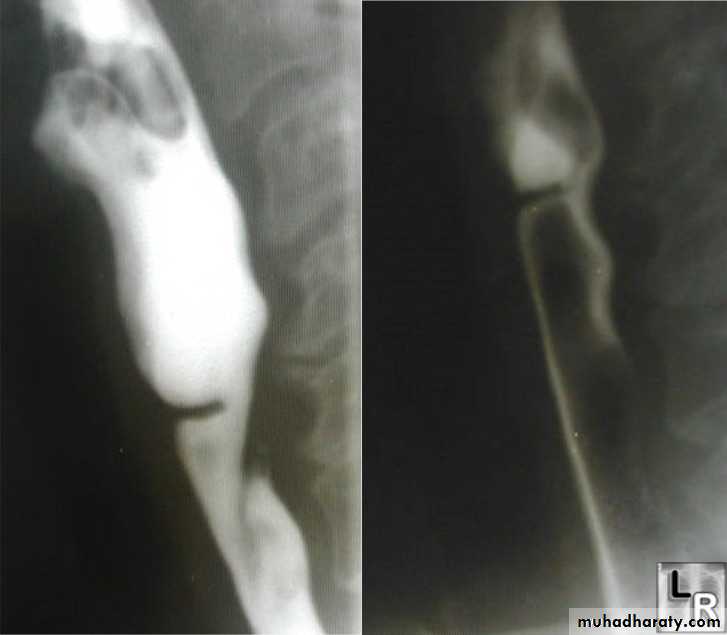

• Ba. swallow :

• 1-Constant narrowing.

• 2- Long length (lower third).

• 3-Smooth and regular.

• 4-Mild proximal dilatation.

• 5-No shouldering sign.

• 6-Smooth tapering

• ( funnel shape).

Benign Stricture